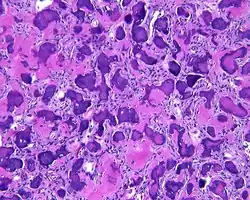

Pathology findings

By microscopic evaluation, the tumors are composed of a variably cellular stroma make up of spindled to stellate fibroblast-like cells. Within this stroma, are numerous small, rounded, mineralized collagenous ossicles and immature osteoid. Many times the curved-shaped bone fragments have a collagenous rim around them. Ossicles may fuse to form much large mineralizations. Cementum-like psammomatous bodies (cementicles) may also be present. Osteoblastic rimming is not uncommon. Occasionally, giant cells and even mitoses are seen.[1][3]